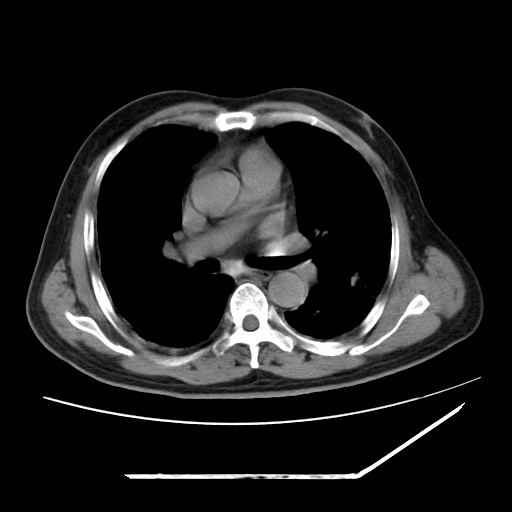

男,57,畏寒,发热

两肺野多发大小不一高密度灶,纵膈内见肿大淋巴结,要考虑转移瘤可能。双侧胸腔少量积液。

双肺多发结节样病灶,部分内见透光区,纵隔内见淋巴结肿大。结核临床如有畏寒,高热,白细胞增高首先考虑迁徙性肺脓肿(多是金黄色葡萄球菌感染)。

注意除外转移瘤。